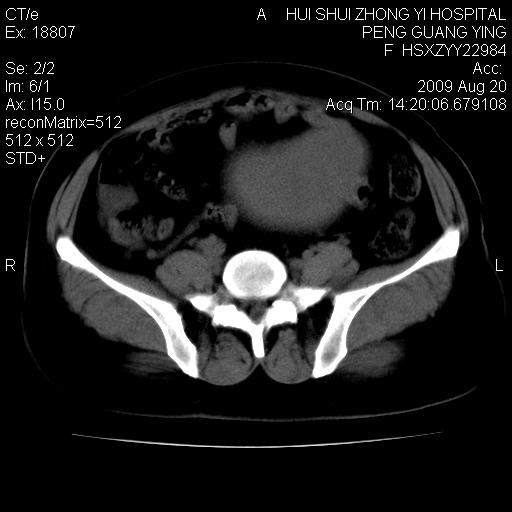

标题: CT21707:女,42岁,因发现下腹部包块2月。 [打印本页]

标题: CT21707:女,42岁,因发现下腹部包块2月。

增强看看,倾向于子宫肌瘤并囊变或腺肌征,宫腔少量积液。

考虑 1 卵巢囊腺瘤 2 子宫肌瘤。

目前的影像表现显示肿块位于腹腔及盆腔,但具体定位,分清来源较困难,是否来源于卵巢、子宫无法定论,子宫直肠及子宫膀胱周围脂肪间隙尚较清晰,如果患者有过腹腔好或者盆腔手术史,也可以形成不典型的血中,最好手术后定为定性,我期待结果。

软组织密度,与子宫一致。双侧卵巢形态、密度好,不支持来源于卵巢。

来源卵巢--畸胎类肿瘤